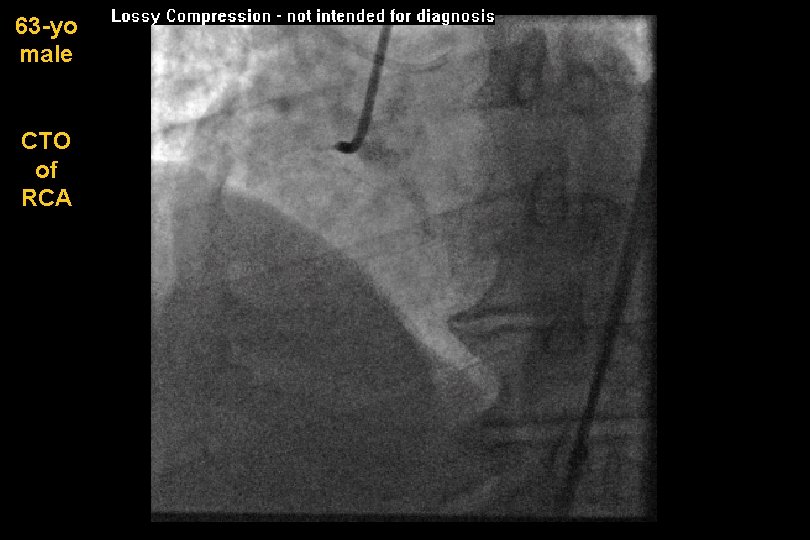

63 -yo male CTO of RCA